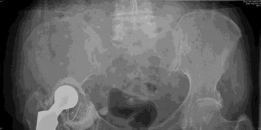

Advanced osteoarthritis bilaterally. Osteonecrosis and complete obliteration of the joint space on both sides…

Case Title: Hybrid Primary Total Hip Arthroplasty Demographics Age: 86 Sex: Female BMI: 25 Relevant Past Medi…